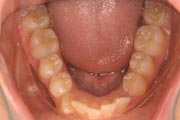

Crowding

Before